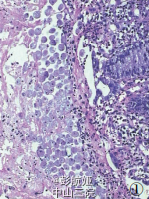

肠阿米巴病1例

彭医师   晋宁区妇幼保健中心

患者男性,20 岁,反复腹泻半年,加重 2周伴少量脓血。体检:肝、脾肋下未触及,全腹无压痛,无包块,无肌紧张,肠鸣音正常,双下肢不肿。实验室检查:大便常规 +OB:OB(±);大便培养+药敏:未培养出病菌;余均正常。B 超:肝、胆、脾、胰正常。病理标本来自肠镜活检组织,经 10% 中性福尔马林固定,常规脱水,石蜡包埋。4μm 厚切片,HE 染色,光镜观察。